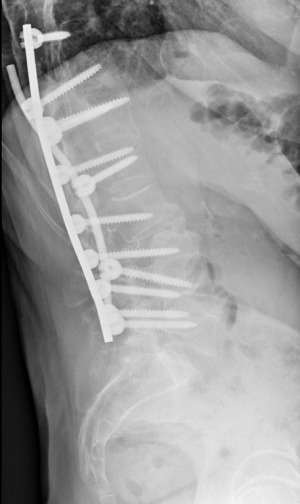

The patient was qualified for surgery due to the progression of the lower curvature and persistent pain. The surgical plan was to perform a posterior spinal fusion in the lumbar region while leaving the upper fused thoracic segment. The fusion levels were determined preoperatively using a “standing X-ray”. MRI was used to determine the spine levels of stenosis in the “flat lying” position as well as root compression at each level. CT was used to confirm the (I) successful fusion in the previously fused levels, (II) determine the entry point and angulation for the screws, (III) check the spine alignment in the lying position and compare it to the standing one in X-ray. Although not performed, the good practice would require determining bone density using H-Score (at least 85) to ensure proper screw purchase and introduction of teriparatide for a 3–6 month period. The patient underwent a Th9-L4 posterior instrumented spinal fusion with correction and derotation using the MESA2 transpedicular screw system with a titanium rod on the right and cobalt-chromium (Co-Cr) on the left. The screws were introduced using “free-hand technique”, fluoroscopy and neuromonitoring checks after each screw. Transverse processes and preoperative CT were used to determine the entry point and screw angulation at each point. The operative and postoperative periods were uneventful. The patient’s postoperative parameters were Cobb’s angle of the lower curve of 47°, sagittal vertical axis (SVA) decreased from 6.5 to 2.5 cm and the coronal balance (CB) from 3 cm right was reduced to 0. Pelvic tilt (PT) changed from 38.5 to 25.5 degrees; the change of sacral slope (SS) remained insignificant. Pelvic incidence-lumbar lordosis (PI-LL) mismatch decreased from 44 to 36.7 degrees.

At 3-month post-surgery check-up, X-rays revealed that the spinal instrumentation had dislodged secondary to osteopenia and torsional forces. The left Co-Cr rod, due to its stiffness, which is higher than the titanium rod, was carrying higher forces onto the screws, which pulled the screws from L4 and L3 out of the pedicles (Figure 3). Revision surgery was performed, the loose screws were taken out and replaced in L4 and L5, and a new titanium rod was placed on this side. Cobb’s angle decreased to 42° after the surgery (Figures 4,5). The patient was discharged as no complications occurred.